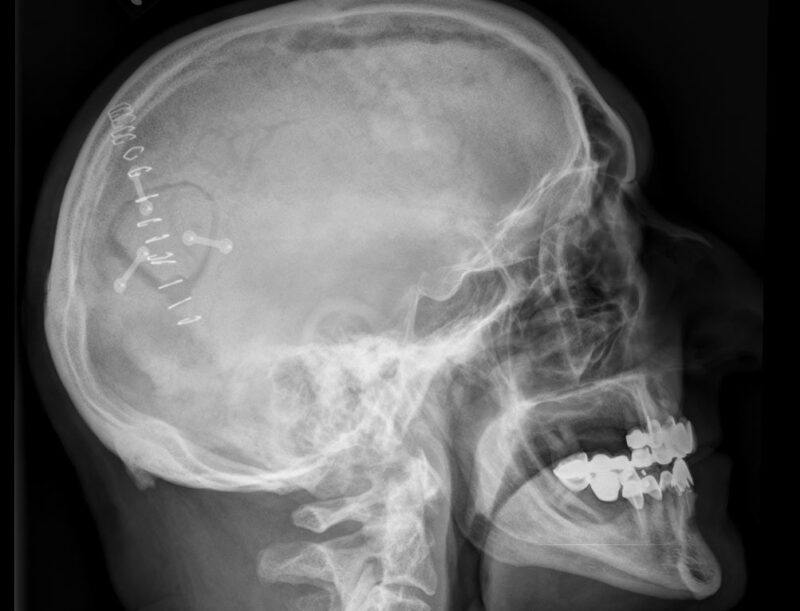

Titanium Plates And Screws Craniotomy . Titanium fixation plates are routinely used for rigid fixation of bone flaps after craniotomy. Craniotomy is a procedure in which a surgeon removes a section of the skull and replaces the piece of bone, or bone flap, immediately afterward using titanium screws and plates. The use of titanium plates and screws for bony reconstruction following craniotomy and craniofacial trauma is a safe. In craniofacial surgery or after craniotomy. When a cranioplasty or craniofacial hardware revision takes place, the titanium or metal hardware screws need to be removed to. To complete an operation performed via craniotomy, the neurosurgeon stitches up the incision in the dura mater and replaces the bone flap, securing it in place with. Craniobridge ® screws offer a secure and stable fit with the screwdriver blade as well as an easy and fast screw insertion. The aim of this study was to assess outcome of bone flap fixation using mini titanium plates and screws.

Fixed skull fractures after road accident. Frontal Xray of a section Titanium Plates And Screws Craniotomy In craniofacial surgery or after craniotomy. Craniobridge ® screws offer a secure and stable fit with the screwdriver blade as well as an easy and fast screw insertion. When a cranioplasty or craniofacial hardware revision takes place, the titanium or metal hardware screws need to be removed to. To complete an operation performed via craniotomy, the neurosurgeon stitches up the. Titanium Plates And Screws Craniotomy.